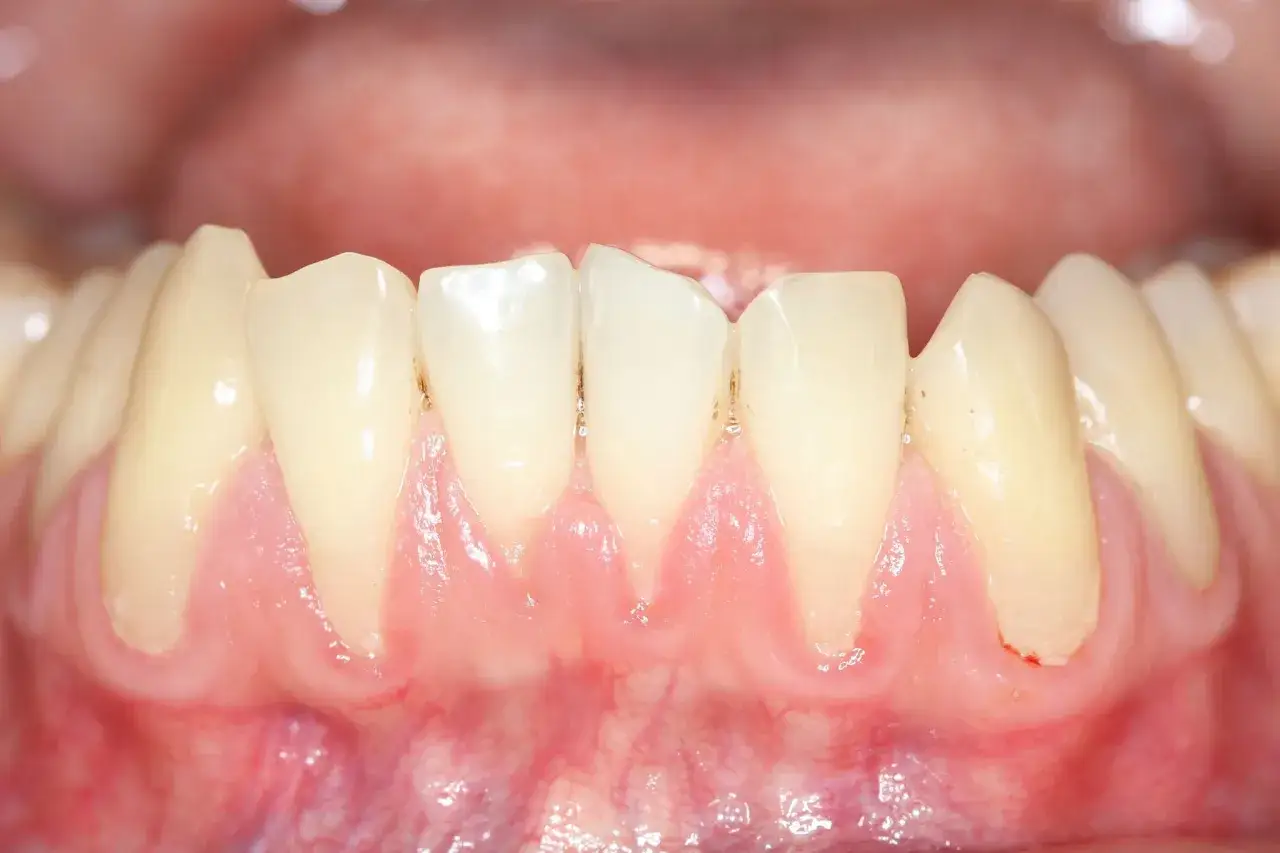

To jedne z najwcześniejszych i najczęściej lekceważonych objawów paradontozy. Krwawienie dziąseł podczas szczotkowania, nitkowania, a nawet jedzenia, jest sygnałem stanu zapalnego. Zdrowe dziąsła nie krwawią. Utrzymujący się nieprzyjemny zapach z ust, czyli halitoza, często jest wynikiem namnażania się bakterii beztlenowych w kieszonkach przyzębnych. Widoczne cofanie się dziąseł (recesja dziąseł) prowadzi do odsłaniania szyjek zębowych, co może skutkować nadwrażliwością na zimno, ciepło czy słodkie pokarmy. Wszystkie te sygnały świadczą o tym, że proces chorobowy postępuje i wymaga uwagi specjalisty.

Gdy paradontoza wchodzi w bardziej zaawansowane stadium, pojawiają się poważniejsze symptomy. Odczuwalna ruchomość zębów to jeden z najbardziej alarmujących znaków, świadczący o znacznej utracie kości podtrzymującej zęby. Pojawienie się ropy z kieszonek dziąsłowych, widoczne przy ucisku na dziąsło, jest oznaką aktywnej infekcji bakteryjnej. Ból podczas nagryzania pokarmów może wskazywać na zapalenie ozębnej lub uszkodzenie tkanek wokół zęba. Wrażenie „wydłużonych” zębów jest bezpośrednim skutkiem recesji dziąseł i utraty kości, co sprawia, że zęby wydają się dłuższe niż w rzeczywistości. Te objawy są jednoznacznymi wskazaniami do pilnej konsultacji ze specjalistą.